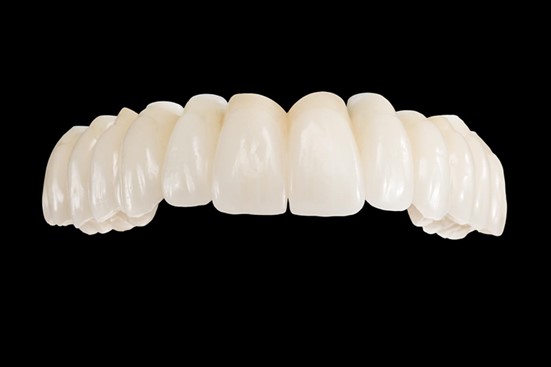

Der festsitzende Zahnersatz wird aus Zirkonoxidkeramik hergestellt. Das leistungsfähige Material ist nicht nur ästhetisch ansprechend und sieht natürlich aus, sondern es ist äußerst stabil, langlebig und biokompatibel. Da die Fertigung des Zahnersatzes sehr anspruchsvoll ist und man viel Erfahrung braucht, arbeiten wir exklusiv mit dem zahntechnischen Meisterlabor König & Weiß zusammen, um höchste Qualität zu garantieren.

Das All-on-8 Behandlungskonzept: Zahnbrücke aus Vollkeramik auf 8 Implantaten für den Oberkiefer

Um einen komplett zahnlosen Oberkiefer mit dem All-on-8 Konzept zu versorgen, benötigt man für festsitzenden Zahnersatz insgesamt 8 Implantate, die im Kiefer verteilt werden. Sofern es sich um herausnehmbaren Zahnersatz handelt, reichen 6 Implantate aus. Damit gehören wackelige Prothesen und Einschränkungen beim Kauen, Sprechen und Lachen der Vergangenheit an. Nach der mehrmonatigen Einheilzeit kann bedenkenlos wieder alles konsumiert werden – ohne Geschmackseinbußen durch Gaumenplatte und Haftcreme. Die Implantate verhelfen außerdem zu einer stabilen und knochenerhaltenden Versorgung mit ästhetisch schönem Zahnersatz aus Zirkonvollkeramik. Von echten Zähnen ist dieser hochwertige Zahnersatz nicht mehr zu unterscheiden, was gesunde und jugendliche Ausstrahlung verleiht.

Bildquelle: ©GZFA Versorgung des Oberkiefers mit einer Keramikbrücke auf 8 Implantaten.